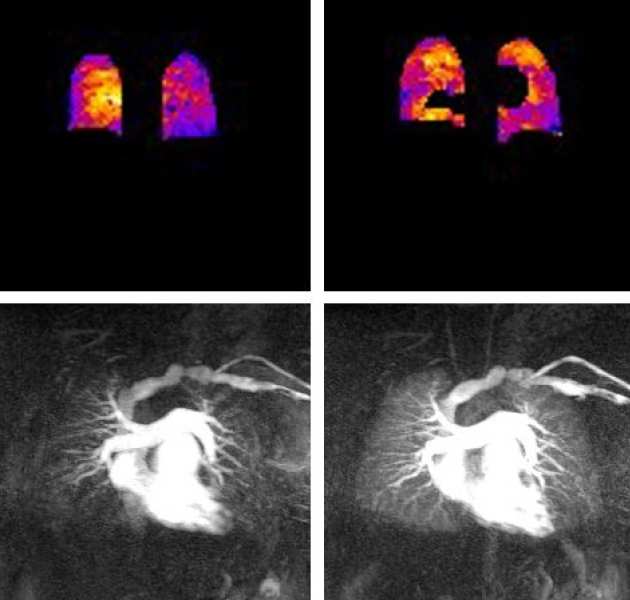

Oxygen-enhanced MRI

We are investigating the use of oxygen-enhanced MRI ventilation mapping in combination with MR perfusion to provide increased diagnostic accuracy when compared with ventilation-perfusion SPECT scintigraphy in patients with pulmonary hypertension.

We are investigating the use of oxygen-enhanced MRI ventilation mapping in combination with MR perfusion to provide increased diagnostic accuracy when compared with ventilation-perfusion SPECT scintigraphy in patients with pulmonary hypertension.